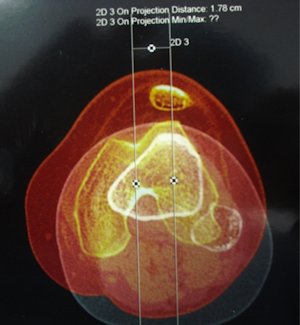

MRG'de transvers kesitler medial patello-femoral ligament hasarının yeri ve patellar dizilimin durumu hakkında önemli bilgiler verir. (Resim 1) Patella hala sublukse ise, troklear displazi ve patella alta varsa, tekrar çıkık olma riski çok yüksektir. Bu hastalarda osteokondral kırık olmasa bile ilk çıkıktan sonra cerrahi tedavi uygulanabilir. MPFL lezyonu patellaya yakın ise artroskopik teknikler uygulanabilir. MPFL lezyonu bağın gövdesinden veya femoral insersiyonundan ise açık teknikler gereklidir.

Q açısının yüksekliği, objektif olarak tibial tüberkül-troklear oluk (TT-TO) mesafesinin ölçümü ile yapılır (Resim 2). Transvers MR kesitlerinde özel yazılımlar kullanılarak yapılan bu ölçümlerde TT-TO mesafesi 2 cm2in üzerindeyse, tek başına proksimal yumuşak doku dizilim cerrahisi yetersiz kalacaktır. Bu durumda proksimal cerrahi girişimlere ek olarak tibial tüberkülün medializasyon osteotomisi yapılmalıdır.